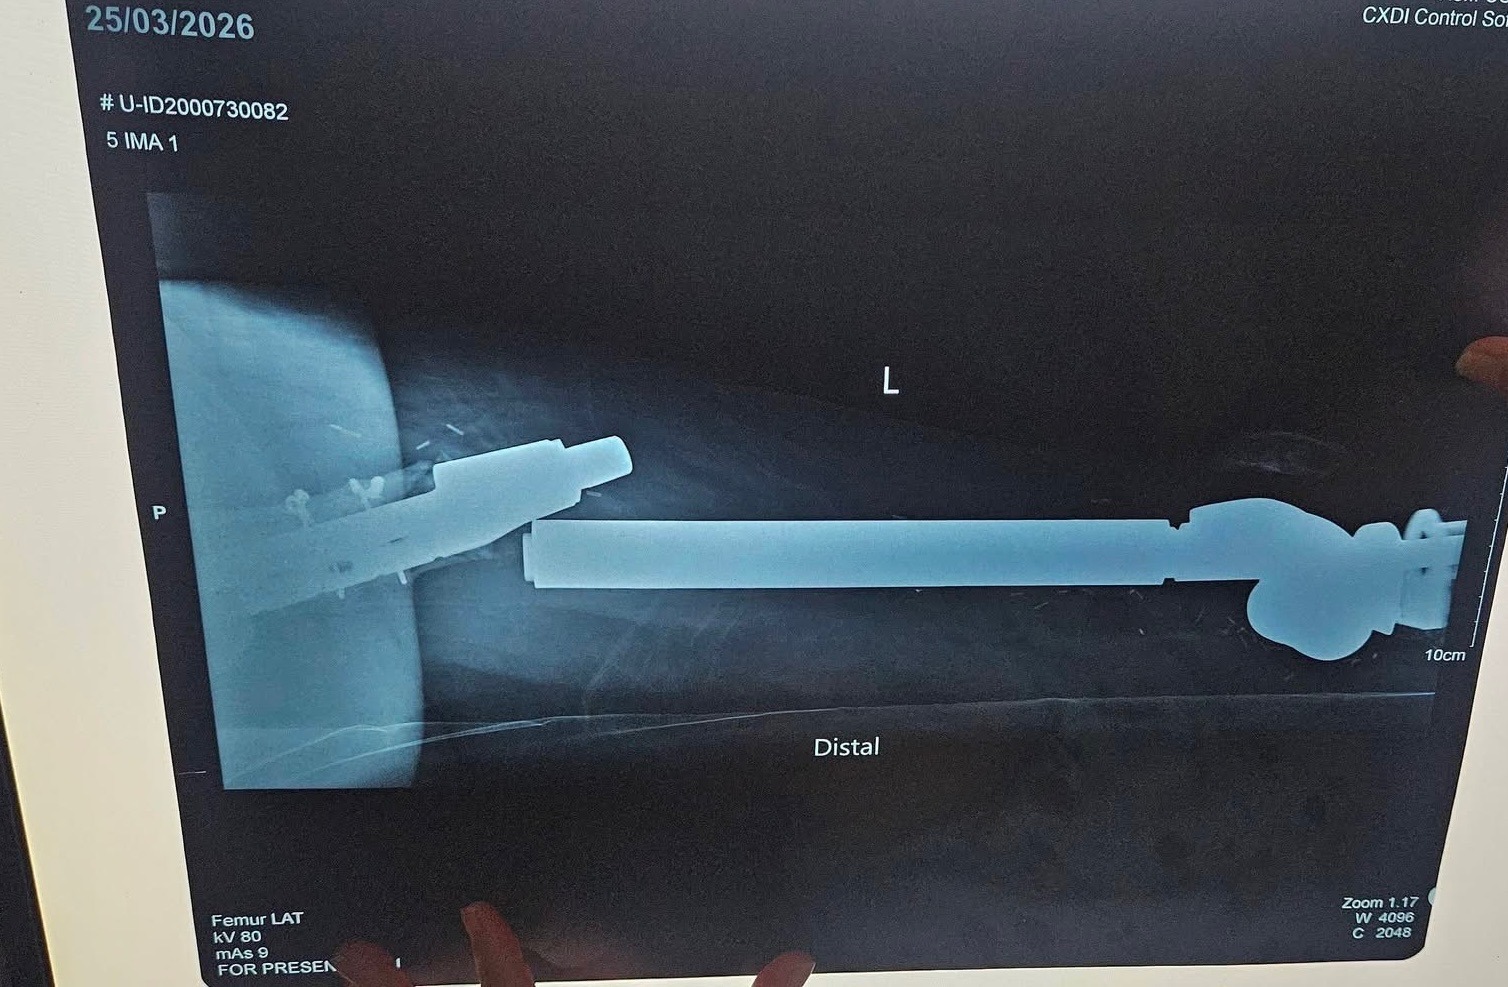

Unfortunately, another hurdle in life has presented itself before her. Her prosthesis has broke internally resulting her inability to move her leg at all and is extremely painful. She is currently waiting to hear from her doctor who is tirelessly looking for a replacement of the screw that had broken off. It has been decades since the prosthesis was surgically placed, chances of finding the part is slim. Surgery to replace the screw is costly… but if they are unable to find the exact replacement then they will need to replace the whole entire prosthesis, which is unimaginably more expensive… Michelle and her mother are trying their best to ask the Filipino government for help and is jumping through hoops to obtain any financial support. But as you can guess, it can be lengthy and straining. I fear that the longer she waits, the higher chance of her encountering complications, especially circulation issues, will put her limb at risk.

In the middle of her meeting, Mich suddenly had to be rushed to the hospital. After consultation and x-ray, we found out that na nabali yung leg prosthesis niya. Hindi na po niya maramdaman ung lower leg niya, and because of this, Mich currently cannot walk or put weight on her left leg. For now, she is confined to the bed and can only move using crutches or a wheelchair as advised by her doctors.

We’ve been advised that her prosthesis now needs to be fully replaced. It needs to be ordered and imported which will take time. Wala pa pong exact amount na masabi ang doctors dahil customized pa ito kay Mich, but we are trusting God as we begin to prayerfully prepare and pag-ipunan ang kanyang replacement.